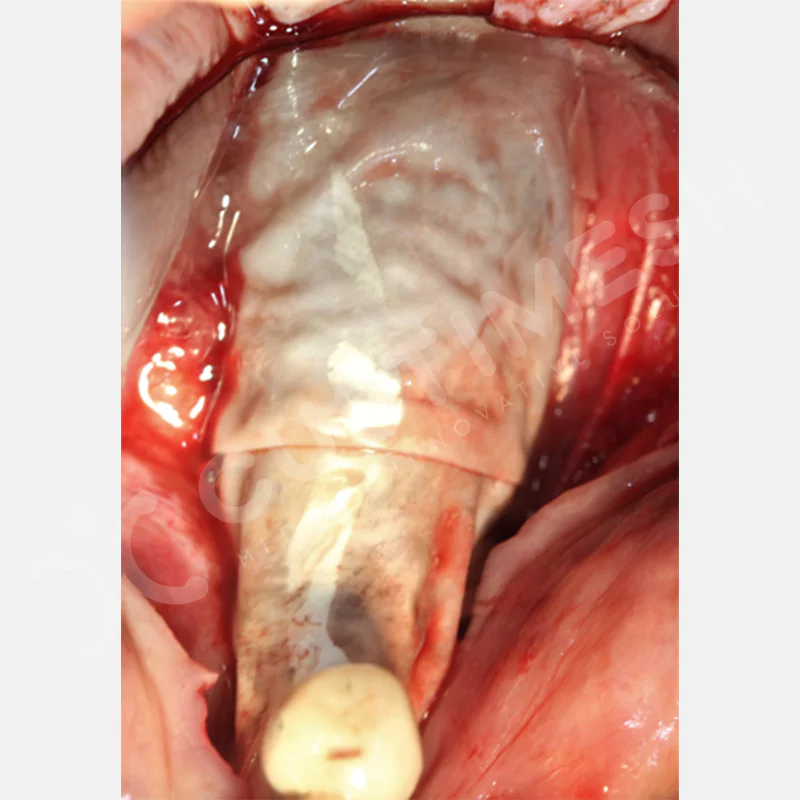

VAKA 1

VAKA 2

VAKA 3